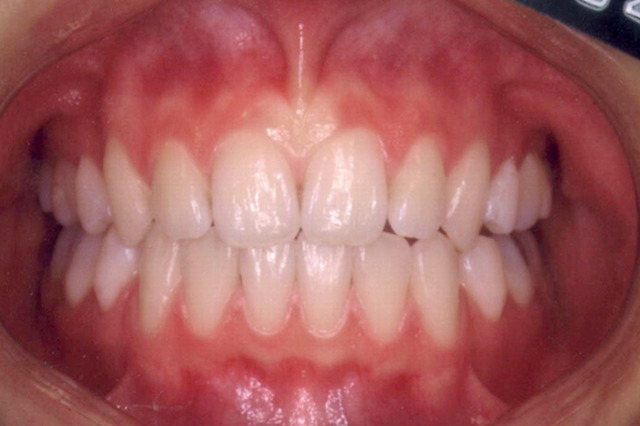

下顎前突 治療前

主訴 顎が出ていて見た目が気になる

診断名あるいは主な症状 下顎前突

年齢 11歳9ヶ月

治療に用いた主な装置 ブラケット装置 スタンダードエッジワイズ法

抜歯部位 非抜歯

治療期間 3年2ヶ月

治療費概算 70万+月々の調整料

リスク副作用 歯の根が吸収して短くなる場合があります。

歯茎が痩せて下がる場合があります。

舌で歯を押す唇を噛む等の癖が改善されない場合は、治療期間が長引く場合があります。

定期的に通院できない、キャンセルが多い場合は治療期間が長引きます。